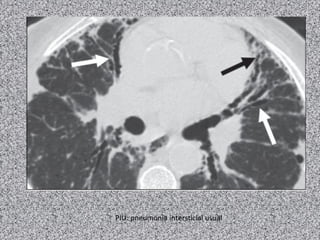

PIU: pneumonia intersticial usual